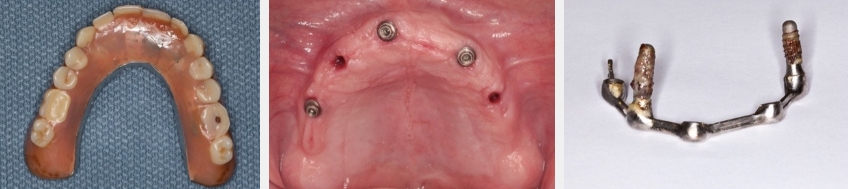

Neither of these papers reported on the influence of the prosthetic design of the mandibular overdentures utilized. Is there a difference in implant success or survival when a passive fitting tissue bar is used rather than resilient individual attachments, like locator or spherical attachments? An article from Elsyad et al. (2021) sheds light on this question by comparing overdentures with immediately loaded implants, “resilient stud” locator attachments, and a bar attachment. In this study, four implants were used in the mandible. At one year, the authors report implant survival as 96.6% for the locator and 98.3% for the passive fitting bar — no statistical difference.

- “Current clinical research supports high survival using threaded, microtextured implants with a minimum diameter of 3.0 mm to support overdenture prostheses when used with immediate, early, or conventional loading protocols. Limited evidence exists for immediate loading of implants supporting overdentures in the maxilla.” 4

- “Descriptive material from the review in this group for immediate loading by Schimmel et al lists inclusion criteria of: insertion torque (≥ 30 Ncm), ISQ value (≥ 60), two or more implants in the mandible, or four or more implants in the maxilla.”4

- “Splinting of implants and the type of attachment system did not affect 1-year survival rate compared to freestanding implants.”4